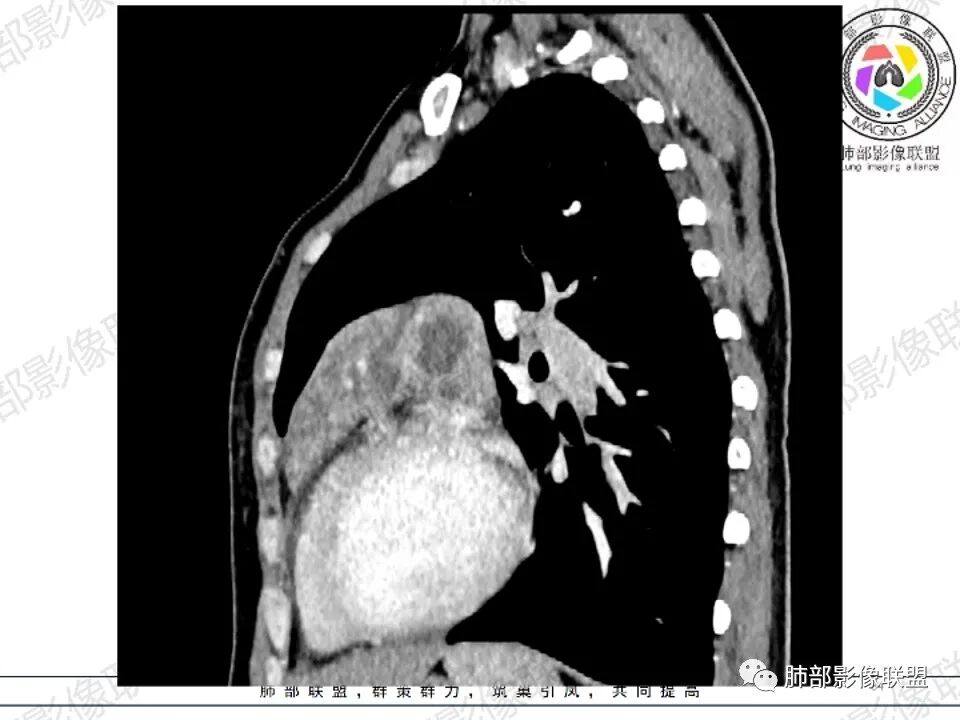

纵隔多发结节堆积 塑型生长  质软 边界不清 强化不均  双侧腋窝淋巴结肿大

年轻女性,贫血伴乏力,前纵隔占位,多发结节融合成块,爬孵感,边界模糊,不均匀强化,中心坏死,内可见血管造影,部分侵犯心包,双侧腋窝多发肿大淋巴结,首先考虑淋巴瘤

年轻女性,贫血,CT示前纵隔团片状软组织占位,多结节堆积感,塑形生长,边界欠清,包绕大血管及心包,增强明显不均匀强化,内见血管漂浮。纵隔4R,5,7区及双侧腋窝多发肿大淋巴结,综合考虑为淋巴瘤可能

前纵隔不规则肿块,多结节融合,边界欠清,延周围脂肪间隙生长,包绕主动脉及肺动脉血管,平扫密度欠均匀,增强扫描可见多发低密度坏死,并可见一条血管穿行,腋窝多发大小不等淋巴结肿大,年轻女性,考虑恶性:淋巴瘤,胸腺癌,肉瘤,浆细胞瘤

病灶两叶,相对独立,中央相连

整体还是胸腺的形态

边缘平直为主,稍膨隆,但是无明显的局限性凸起

囊变区域弥漫,大部分直达壁,分界不清,部分分界清楚

内部血管走形自然

女,27,间断头晕、乏力3年,左眼视物模糊2月。贫血。胸部CT:前纵隔不规则肿块,多结节融合,边界不清,沿主动脉及肺动脉间隙生长,平扫密度欠均匀,增强扫描可见多发低密度坏死,纵隔血管供血穿行,腋窝多发大小不等淋巴结肿大。考虑恶性病变,胸腺癌?肉瘤?淋巴瘤?鉴别胸腺瘤、结节病等。

前纵隔和双侧腋窝多发的淋巴结肿大,前纵隔为甚,融合呈中等强化,部分坏死呈低密度,包埋肺动脉主干和左心缘,融合斑块状,内见血管飘浮特点,前纵隔脂肪间隙混浊,首选淋巴瘤!

CT:定位纵膈病变,前中纵隔多发肿块,质软,塑形,密度不均匀,边界清楚。增强不均匀强化,坏死边界清楚,血管漂浮征。双侧腋下多组淋巴结肿大,明显异常强化。

2.影像显示前纵隔不规则块状影,依势贴附心脏大血管旁,密度不均,边界不甚清楚,有结节融合感。

3.病灶轻度不均匀强化,可见血管穿行,散在液性低密度区。

双肺门未见肿大淋巴结。

4.双侧腋窝区见增大淋巴结,边界清楚。

1.年轻女性,前纵隔不规则块状影,密度不均,边界不甚清楚,有结节融合感,轻度不均匀强化,可见血管穿行,最常见最符合的无疑是淋巴瘤!